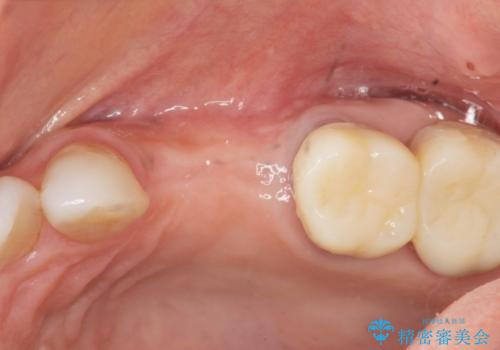

インプラント治療を行うにはインプラント周囲に十分な骨の幅・高さが必要です。

今回はが原因で失われてしまった骨の幅を回復することで長期的な予後を見込めるインプラント治療を行うことができました。